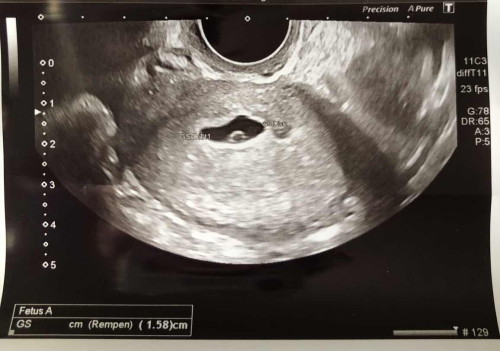

อายุครรภ์ 7 สัปดาห์

สวัสดีค่าแม่แม่ ตอนนี้อายุครรภ์ ถ้านับเอง ครบ 7สัปดาห์พอดีค่ะ วันนี้ไปอัลตราซาว คุณหมอบอกว่าเห็นถุงตั้งครรภ์ประมาณ 12 mm และเห็นถุงไข่แดงแต่ยังไม่เห็นตัวอ่อน อีก 2สัปดาห์ค่อยมาซาวใหม่ ถ้าไม่เจออาจจะเป็นท้องลมค่ะ พอถามหมอว่าอายุครรภ์ตรง 7w มั้ย หมอบอกว่า เครื่องนี้ไม่สามารถบอกอายุครรภ์จากถุงตั้งครรภ์ได้ ต้องเห็นตัวเด็กเท่านั้น ตอนนี้ให้นับเองว่า 7w ไปก่อน มีแม่บ้านไหนอายุครรภ์ 7สัปดาห์แล้วยังไม่เห็นน้องบ้างมั้ยคะ นี่ท้องที่ 3 แล้วค่า 2 ท้องแรก แท้งหมดเลยย 🥹🙏 #ขอบคุณสำหรับคำคอมเม้นล่วงหน้าค่ะ